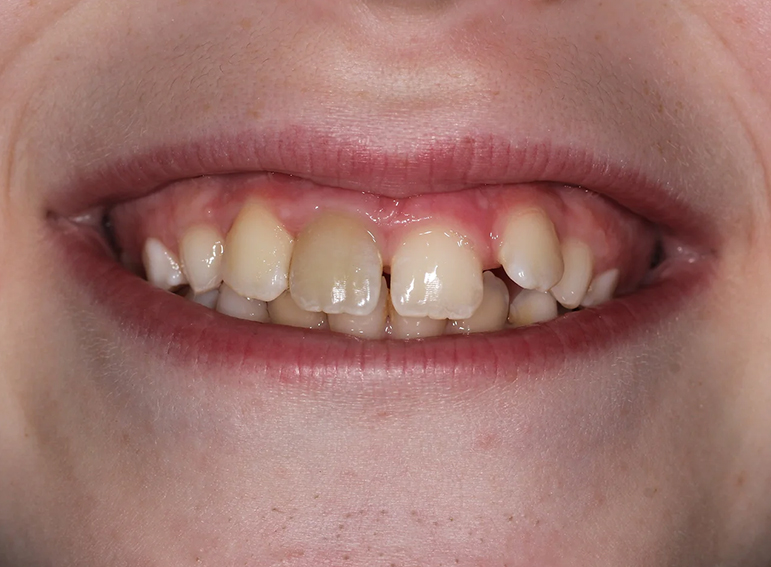

Case 1 – Children

Root filling of an immature tooth and bleaching.